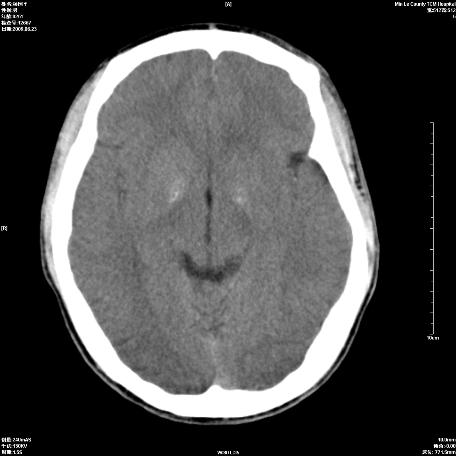

以下是引用随光逐影在2009-6-23 14:30:00的发言:[br]1)颅脑ct轴位平扫颅内未见明确异常。2)左侧额部头皮软组织肿胀。[br][br](双侧苍白球见对称性钙斑,透明隔间腔与vergae腔并存)